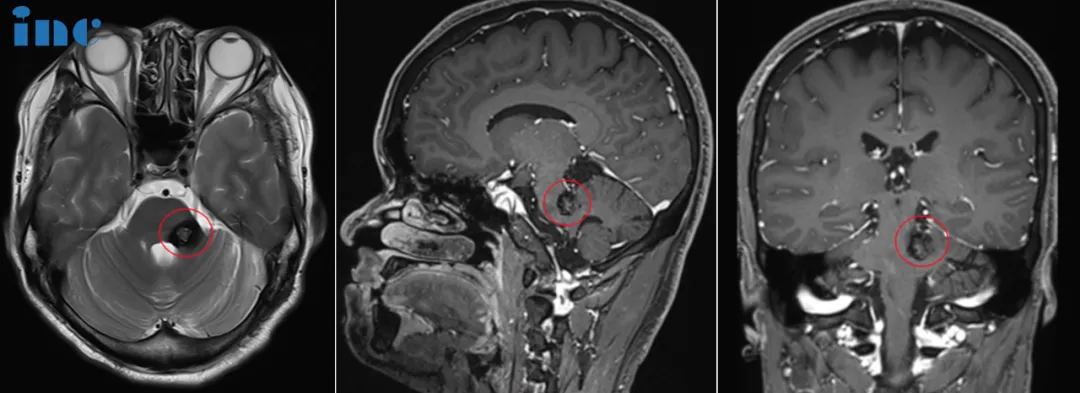

中脑脑干部位存在占位性病变,呈现混杂信号,考虑为海绵状血管瘤的可能性较大。影像学特征表明这符合反复少量出血后的改变,这意味着在此之前,晶晶可能已经发生过几次轻微的脑干出血,...